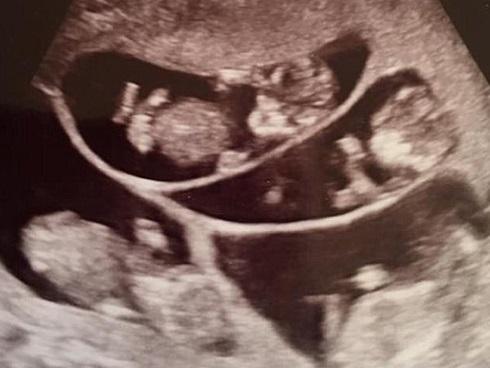

Đang cố thụ thai đứa con thứ 4, bà mẹ choáng váng khi mang bầu một lúc 6 thai

Ca mang thai 6 em bé của bà mẹ này dự định sẽ chào đời vào tháng 2 năm sau.